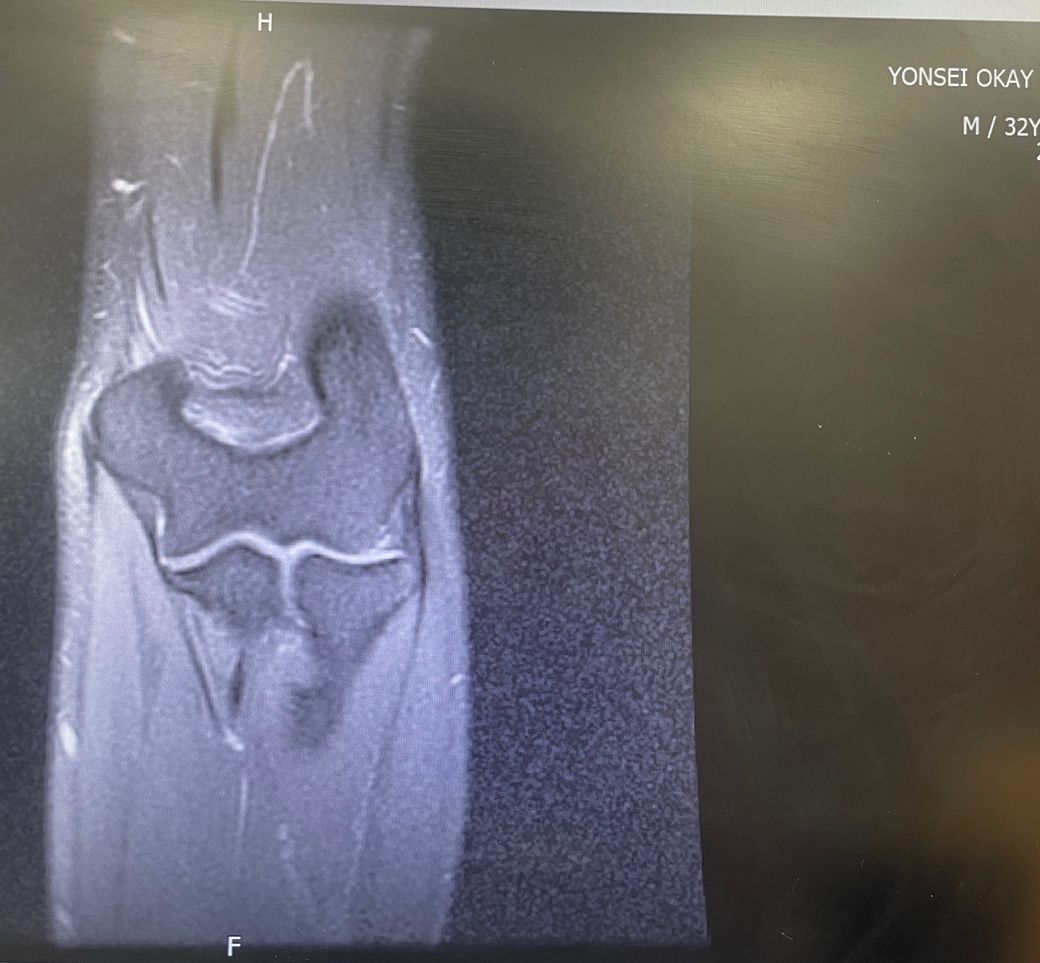

팔꿈치 추벽증후군이 의심되어 MRI 찍었습니다.

팔을 굽혔다 폈다할때 90도 이상 넘어갈때 기타줄 튕기는 것처럼 팅 팅 소리가 나면서

걸리는 느낌이 있었습니다. 유튜브 보고 동네정형외과 가서 MRI 찍었는데 역시 똑같이 저 삼각형이 자리잡고있네용...

추벽증후군은 반드시 수술해야 하는 건가요?? 저는 통증은 없습니다. 소리만 날 뿐

근데 지속적인 마찰로 연골이 마모 될 수 있고 그 후엔 만성통증이 생길 수 있다고 하는데